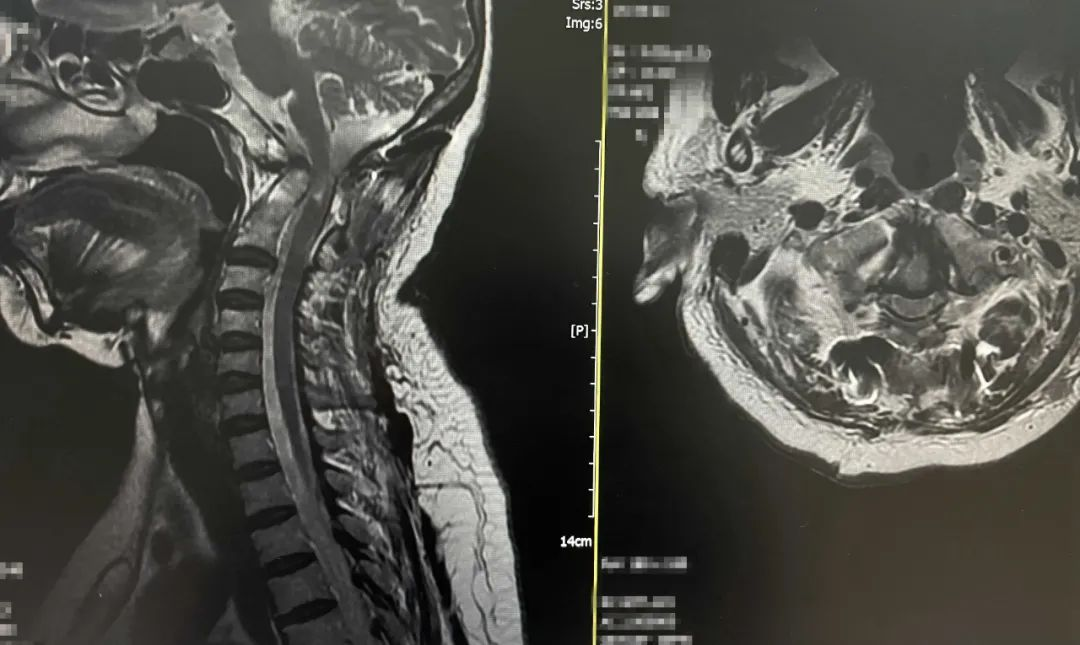

▲术前MRI

患者女性,63岁,不久前不慎摔伤,头部着地后当即颈项部疼痛,伴四肢麻木无力,随后到我院门诊脊柱外科就诊,入院时呈现不全瘫状态,四肢肌力差,左侧肢体肌力减退明显,双上肢感觉减退,无法正常行走,经常性头晕头痛,生活质量差。入院后经详细查体及影像学检查,发现该患者患有颅底凹陷症并颈脊髓缺血,寰枕先天性融合畸形、枢椎与颈3锥体先天性融合畸形、双侧额叶散在小缺血灶、右椎动脉先天性发育纤细,病情复杂。